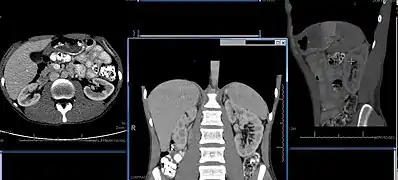

- Normal adult right kidney as seen on abdominal ultrasound with a pole to pole measurement of 9.34 cm.

Renal ultrasonography is essential in the diagnosis and management of kidney-related diseases.[44] Other modalities, such as CT and MRI, should always be considered as supplementary imaging modalities in the assessment of renal disease.[44]